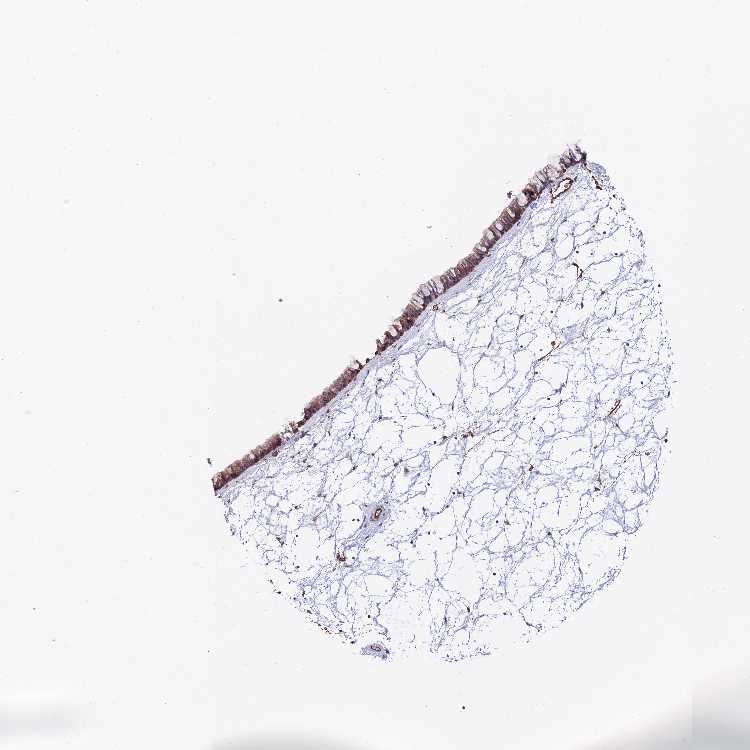

Antibody staining in the annotated cell types in the current human tissue is reported as not detected, low, medium, or high. This score is based on the staining intensity and fraction of stained cells.